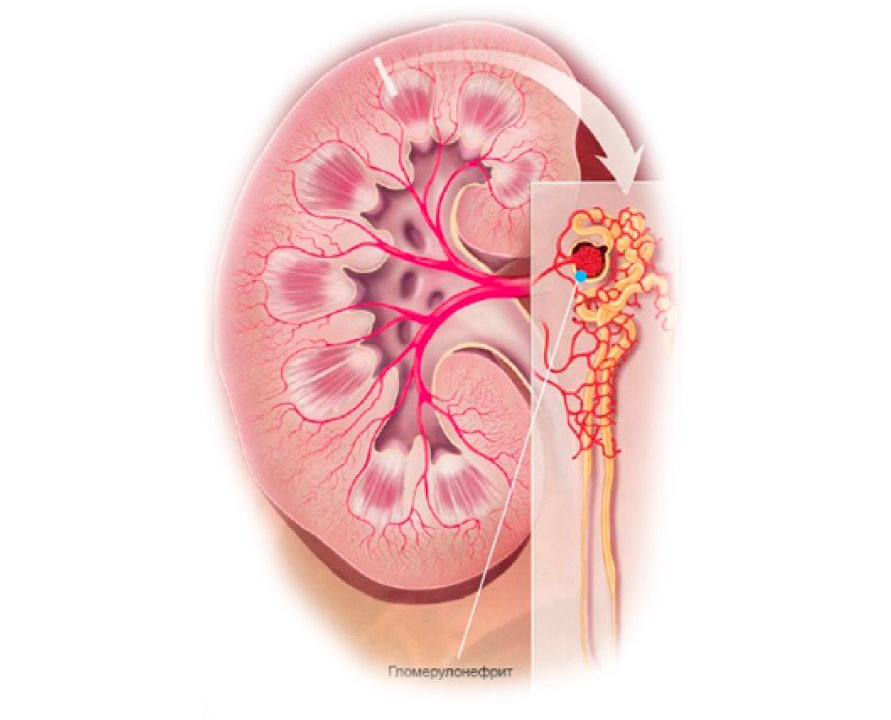

Механизм остро го диффузного гломерулонефрита